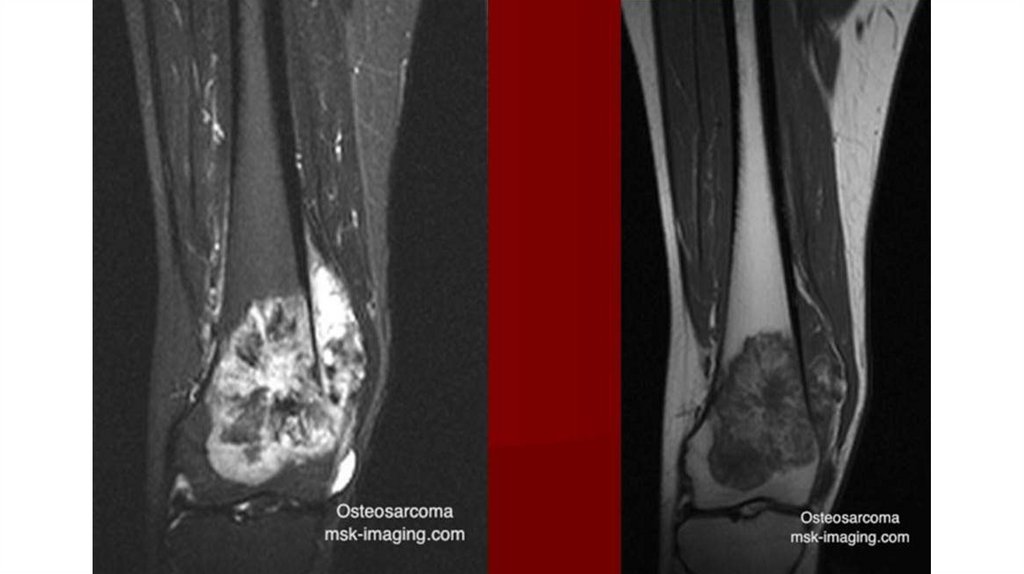

Диагностика

• Рентгенография (очаг деструкции, игольчатый периостит,

«козырек» Кодмана)

• КТ

• МРТ с контрастированием

• Сцинтиграфия с технецием

• Биопсия (высокий полиморфизм с наличием большого количества

митозов, наличие новообразованных остеоидных структур)

• Поиск метастазов